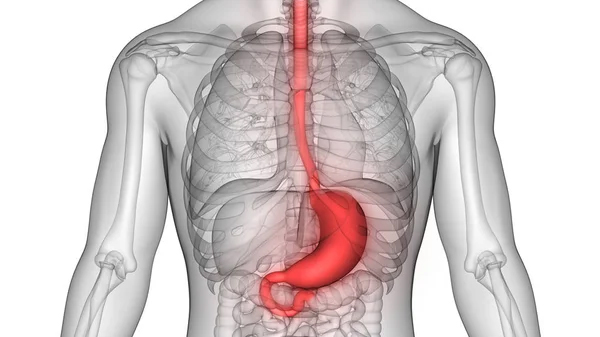

También conocido como cáncer gástrico, es una enfermedad en la que se forman células malignas en el revestimiento del estómago. Es una enfermedad grave que puede extenderse a otras partes del cuerpo y causar complicaciones graves si no se trata a tiempo.

Los síntomas del cáncer de estómago pueden variar y pueden incluir indigestión, dolor abdominal, náuseas, vómitos, pérdida de apetito, pérdida de peso y fatiga. Sin embargo, estos síntomas también pueden ser causados por otras condiciones, por lo que es importante hacerse revisar por un médico si se experimentan estos síntomas.

Hay varios factores de riesgo que pueden aumentar la probabilidad de desarrollar cáncer de estómago, incluyendo la edad avanzada, el tabaquismo, la obesidad, una dieta alta en sal y alimentos ahumados, el historial familiar de cáncer de estómago, la infección por la bacteria Helicobacter pylori y ciertos trastornos genéticos.

El tratamiento del cáncer de estómago puede incluir cirugía para extirpar el tumor, radioterapia y quimioterapia. La elección del tratamiento dependerá de la etapa y la gravedad del cáncer, así como de la salud general del paciente.

En resumen, el cáncer de estómago es una enfermedad grave que puede tener síntomas vagos y puede ser difícil de detectar en las etapas tempranas. Si se sospecha de la presencia de cáncer de estómago, es importante buscar atención médica inmediata para recibir un diagnóstico y tratamiento adecuados.

La dispepsia es un término médico que se utiliza para describir los síntomas de malestar y dolor en la parte superior del abdomen que pueden incluir acidez estomacal, dolor abdominal, sensación de plenitud, náuseas y eructos. A menudo se conoce como indigestión.

La dispepsia puede ser causada por varios factores, como el estrés, la ansiedad, una dieta inadecuada, comer en exceso, el consumo de alcohol o tabaco, la infección por Helicobacter pylori, enfermedades del tracto gastrointestinal, y ciertos medicamentos. En algunos casos, la causa de la dispepsia puede ser desconocida.

El tratamiento de la dispepsia depende de la causa subyacente y puede incluir cambios en la dieta y el estilo de vida, como evitar alimentos picantes o grasos, comer comidas más pequeñas y frecuentes, y reducir el consumo de alcohol y tabaco. Los medicamentos también pueden ser recetados, como antiácidos, inhibidores de la bomba de protones, y otros medicamentos que reducen la inflamación o la motilidad del tracto gastrointestinal.

En resumen, la dispepsia es un término médico que se refiere a los síntomas de malestar en el abdomen superior, y puede ser causada por varios factores. El tratamiento dependerá de la causa subyacente y puede incluir cambios en la dieta y el estilo de vida, así como el uso de medicamentos. Si experimentas síntomas de dispepsia, es importante consultar a un médico para recibir un diagnóstico y tratamiento adecuados.

La gastritis es una inflamación de la mucosa que recubre el estómago. Esta inflamación puede ser causada por varios factores, incluyendo infecciones bacterianas, el uso prolongado de medicamentos antiinflamatorios no esteroideos (AINEs), el consumo excesivo de alcohol, el estrés crónico y el reflujo biliar. Los síntomas de la gastritis pueden incluir dolor abdominal, náuseas, vómitos, pérdida de apetito y sensación de plenitud después de comer. El tratamiento de la gastritis puede incluir cambios en la dieta, medicamentos para reducir la acidez estomacal y la eliminación de la causa subyacente de la inflamación. Si la gastritis no se trata, puede llevar a complicaciones como úlceras gástricas y sangrado gastrointestinal.

La enfermedad por reflujo gastroesofágico (ERGE) es un trastorno del sistema digestivo que ocurre cuando el contenido del estómago, incluyendo los ácidos digestivos, fluye hacia el esófago. El esófago es el tubo que conecta la garganta con el estómago. El reflujo ácido puede causar síntomas como acidez estomacal, dolor en el pecho, regurgitación, tos, dolor de garganta y dificultad para tragar.

La ERGE puede ser causada por una variedad de factores, incluyendo un esfínter esofágico inferior (EEI) debilitado, un músculo que normalmente cierra el extremo inferior del esófago y evita que los ácidos del estómago suban al esófago. Otros factores pueden incluir obesidad, embarazo, hernia de hiato, fumar y comer comidas grandes o grasosas.

El tratamiento para la ERGE puede incluir cambios en la dieta y el estilo de vida, como evitar comidas grandes y grasosas, no acostarse después de comer, y elevar la cabeza de la cama durante el sueño. También pueden recetarse medicamentos como inhibidores de la bomba de protones, antagonistas H2 y antiácidos para reducir la cantidad de ácido producido por el estómago.

En casos graves, puede ser necesaria la cirugía para corregir el problema del EEI debilitado. Si experimentas síntomas de ERGE, es importante buscar atención médica para recibir un diagnóstico y tratamiento adecuados, ya que el reflujo ácido prolongado puede dañar el esófago y aumentar el riesgo de cáncer de esófago.

En resumen, la enfermedad por reflujo gastroesofágico es un trastorno del sistema digestivo que ocurre cuando el contenido del estómago fluye hacia el esófago, lo que puede causar síntomas como acidez estomacal, dolor en el pecho, regurgitación y dificultad para tragar. El tratamiento puede incluir cambios en la dieta y el estilo de vida, así como medicamentos y, en casos graves, cirugía. Si experimentas síntomas de ERGE, es importante buscar atención médica para recibir un diagnóstico y tratamiento adecuados.